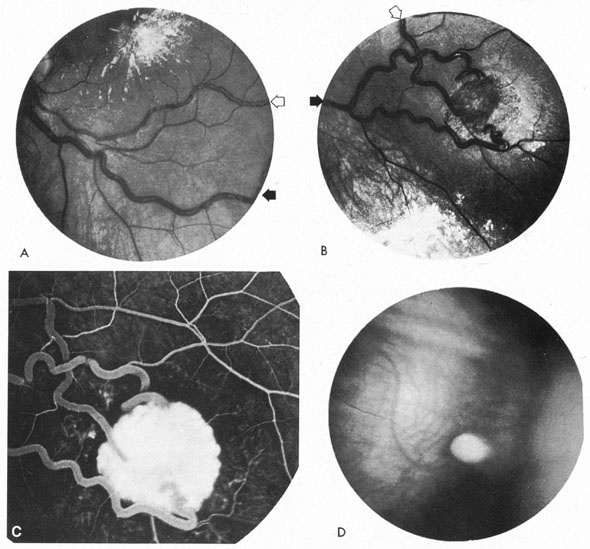

In the fully evolved state, this syndrome includes lid swelling and orbital pain, varying degrees of pulsating exophthalmos, subjective or objective ocular or cephalic bruit, diplopia, engorged and chemotic conjunctiva, and raised intraocular tension. The fundus may show dilated veins without spontaneous pulsations, disc edema, retinal hemorrhages, venous stasis retinopathy or vein occlusions and, rarely, choroidal effusions.104–106 The ophthalmoplegia with carotid–cavernous fistulas is believed to be caused by enlarged muscles or to damage of cranial nerves within the cavernous or petrosal sinus.107 Enlarged extraocular muscles are demonstrable by ultrasongraphy in this form of venous stasis orbitopathy, also utrasonography uncovers reversal of flow in the superion ophthalmic vein.107 Sudden pain with increased swelling, followed by improvement, suggests thrombosis of the superior ophthalmic vein, an event that may be documented by orbital MRI108 or by standardized orbital echography. In addition, proptosis that improves on one side, only to increase on the opposite side, produces a picture of signs and symptoms more marked contralateral to the fistula.109

Anterior segment hypoxia may include protein flare and cells in aqueous, corneal edema, glaucoma, iris rubeosis, rapidly progressive cataract, and venous statis retinopathy, that is, an hypoxic eyeball syndrome. Lesser degrees of congestion with mild conjunctival arterialization (Fig. 15), ocular hypertension, and small abduction defect all hint at the slower flow, lower pressure situation that accrues usually spontaneously with dural circulation fistulas.104,106 Bruit is less likely.

Fig. 15. Dilated tortuous conjunctival vessels in a 63-year-old woman with a presumed dural carotid–cavernous fistula. She presented with a 2-week history of “red eye,” mild retroorbital headache, and double vision. On examination, a left sixth nerve paresis, 3 mm of proptosis, a faint orbital bruit, and slightly elevated intraocular pressure were found. All signs and symptoms resolved spontaneously in 6 weeks, while angiography was being contemplated.

Although the clinical constellation previously described implies the great likelihood of carotid–cavernous fistula, definitive diagnosis depends on complete angiographic evaluation with selective opacification of bilateral internal and external carotid arteries, and vertebral circulation. Prominence of the superior ophthalmic vein is frequently detected on CT scan and MRI, and less frequently extraocular muscle enlargement and lateral bulging of the cavernous sinus are seen by MRI.110 Standardized orbital echography regularly confirms enlargement of the superior ophthalmic vein and increased flow (Fig. 16),107,111 in both direct and indirect fistulas.